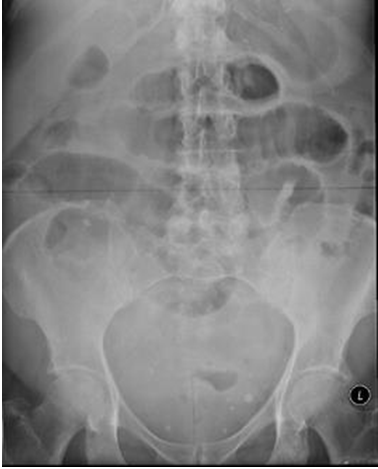

A 73-year-old woman with no prior surgical history presented to the emergency department with a four-day history of abdominal distension, bilious vomiting and not opening her bowels. On physical examination her abdomen was markedly distended, but soft, non-tender with tinkling bowel sounds. Rectal examination revealed no abnormalities. Laboratory findings showed raised inflammatory markers: CRP 123 mg/l and plain film radiography revealed dilated small bowel loops (Figure 1). A CT scan of abdomen and pelvis was subsequently performed which showed dilated small bowel with a transition point in the distal ileum with no definite cause of obstruction identified. Initially, she was managed conservatively with nasogastric tube decompression, intravenous antibiotics and fluids with little improvement of her symptoms. Therefore a diagnostic laparoscopy was undertaken. Intraoperative findings revealed internal herniation of distal ileum through a 3x3 cm defect in the broad ligament of the uterus (Figure 2) and (Figure 3). The small bowel had no evidence of ischaemia therefore was simply reduced and the defect of the broad ligament was closed with 2–0 vicryl stitches (Figure 4). Postoperatively her symptoms completely resolved leading to her discharge after three days.

Figure 1: Abdominal radiograph showing dilated loops of small bowel.